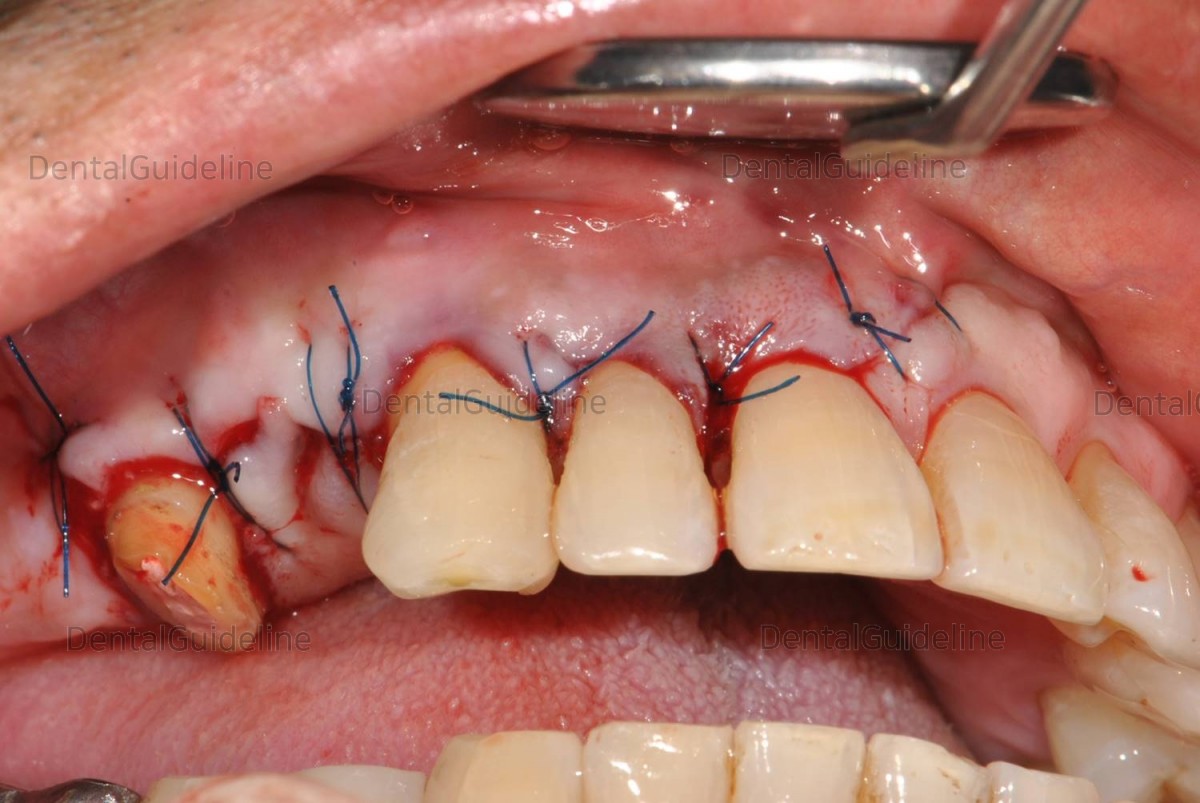

14. Suture.